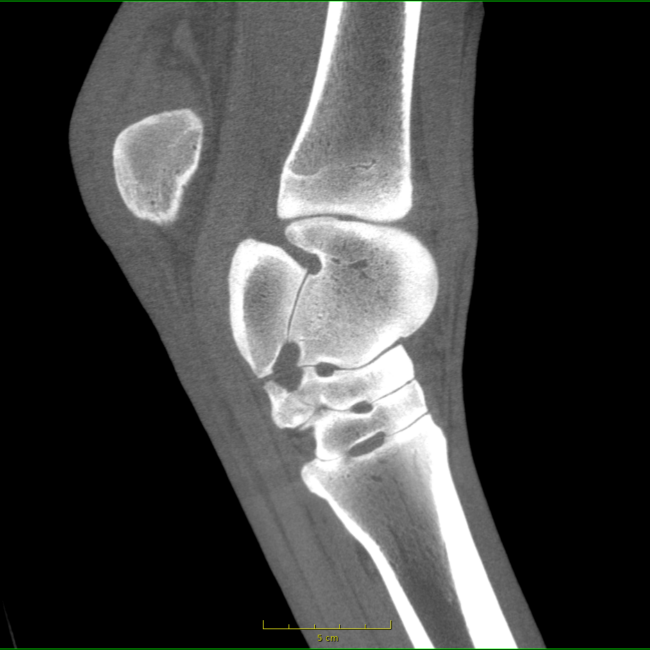

Our High Definition Volumetric Imaging (HDVI) technology represents the most advanced stage of Flat Panel CT technology. It offers exceptional diagnostic imaging for both hard and soft tissues, in diagnostic settings and intraoperative theaters. It is the gold standard for orthopedic applications.

Pegaso enhances safety and usability by enabling the scanning of a standing horse’s head, neck, and limbs.

Scan of the standing horse

Pegaso scans head, neck and limbs of the standing horse